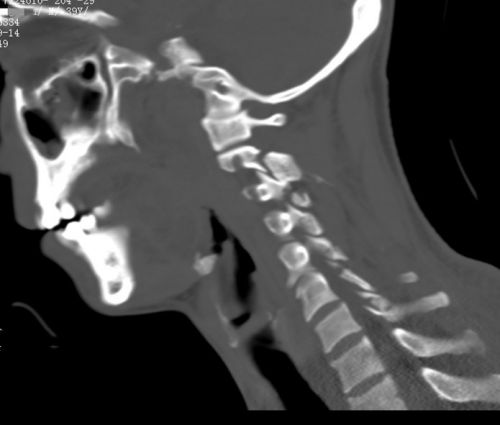

颈部ct显示颈2-胸1椎体多处骨折。